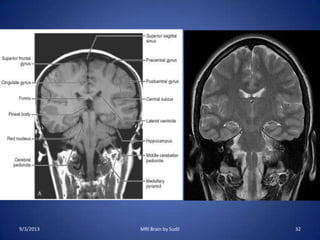

Coronal sequence:

• Plot on sagittal localizer

• Plane perpendicular to

axial plane

• Parallel to posterior

surface of brain stem

• Coverage from anterior

cranial vault to

posterior cranial vault.

9/3/2013 MRI Brain by Sudil 32